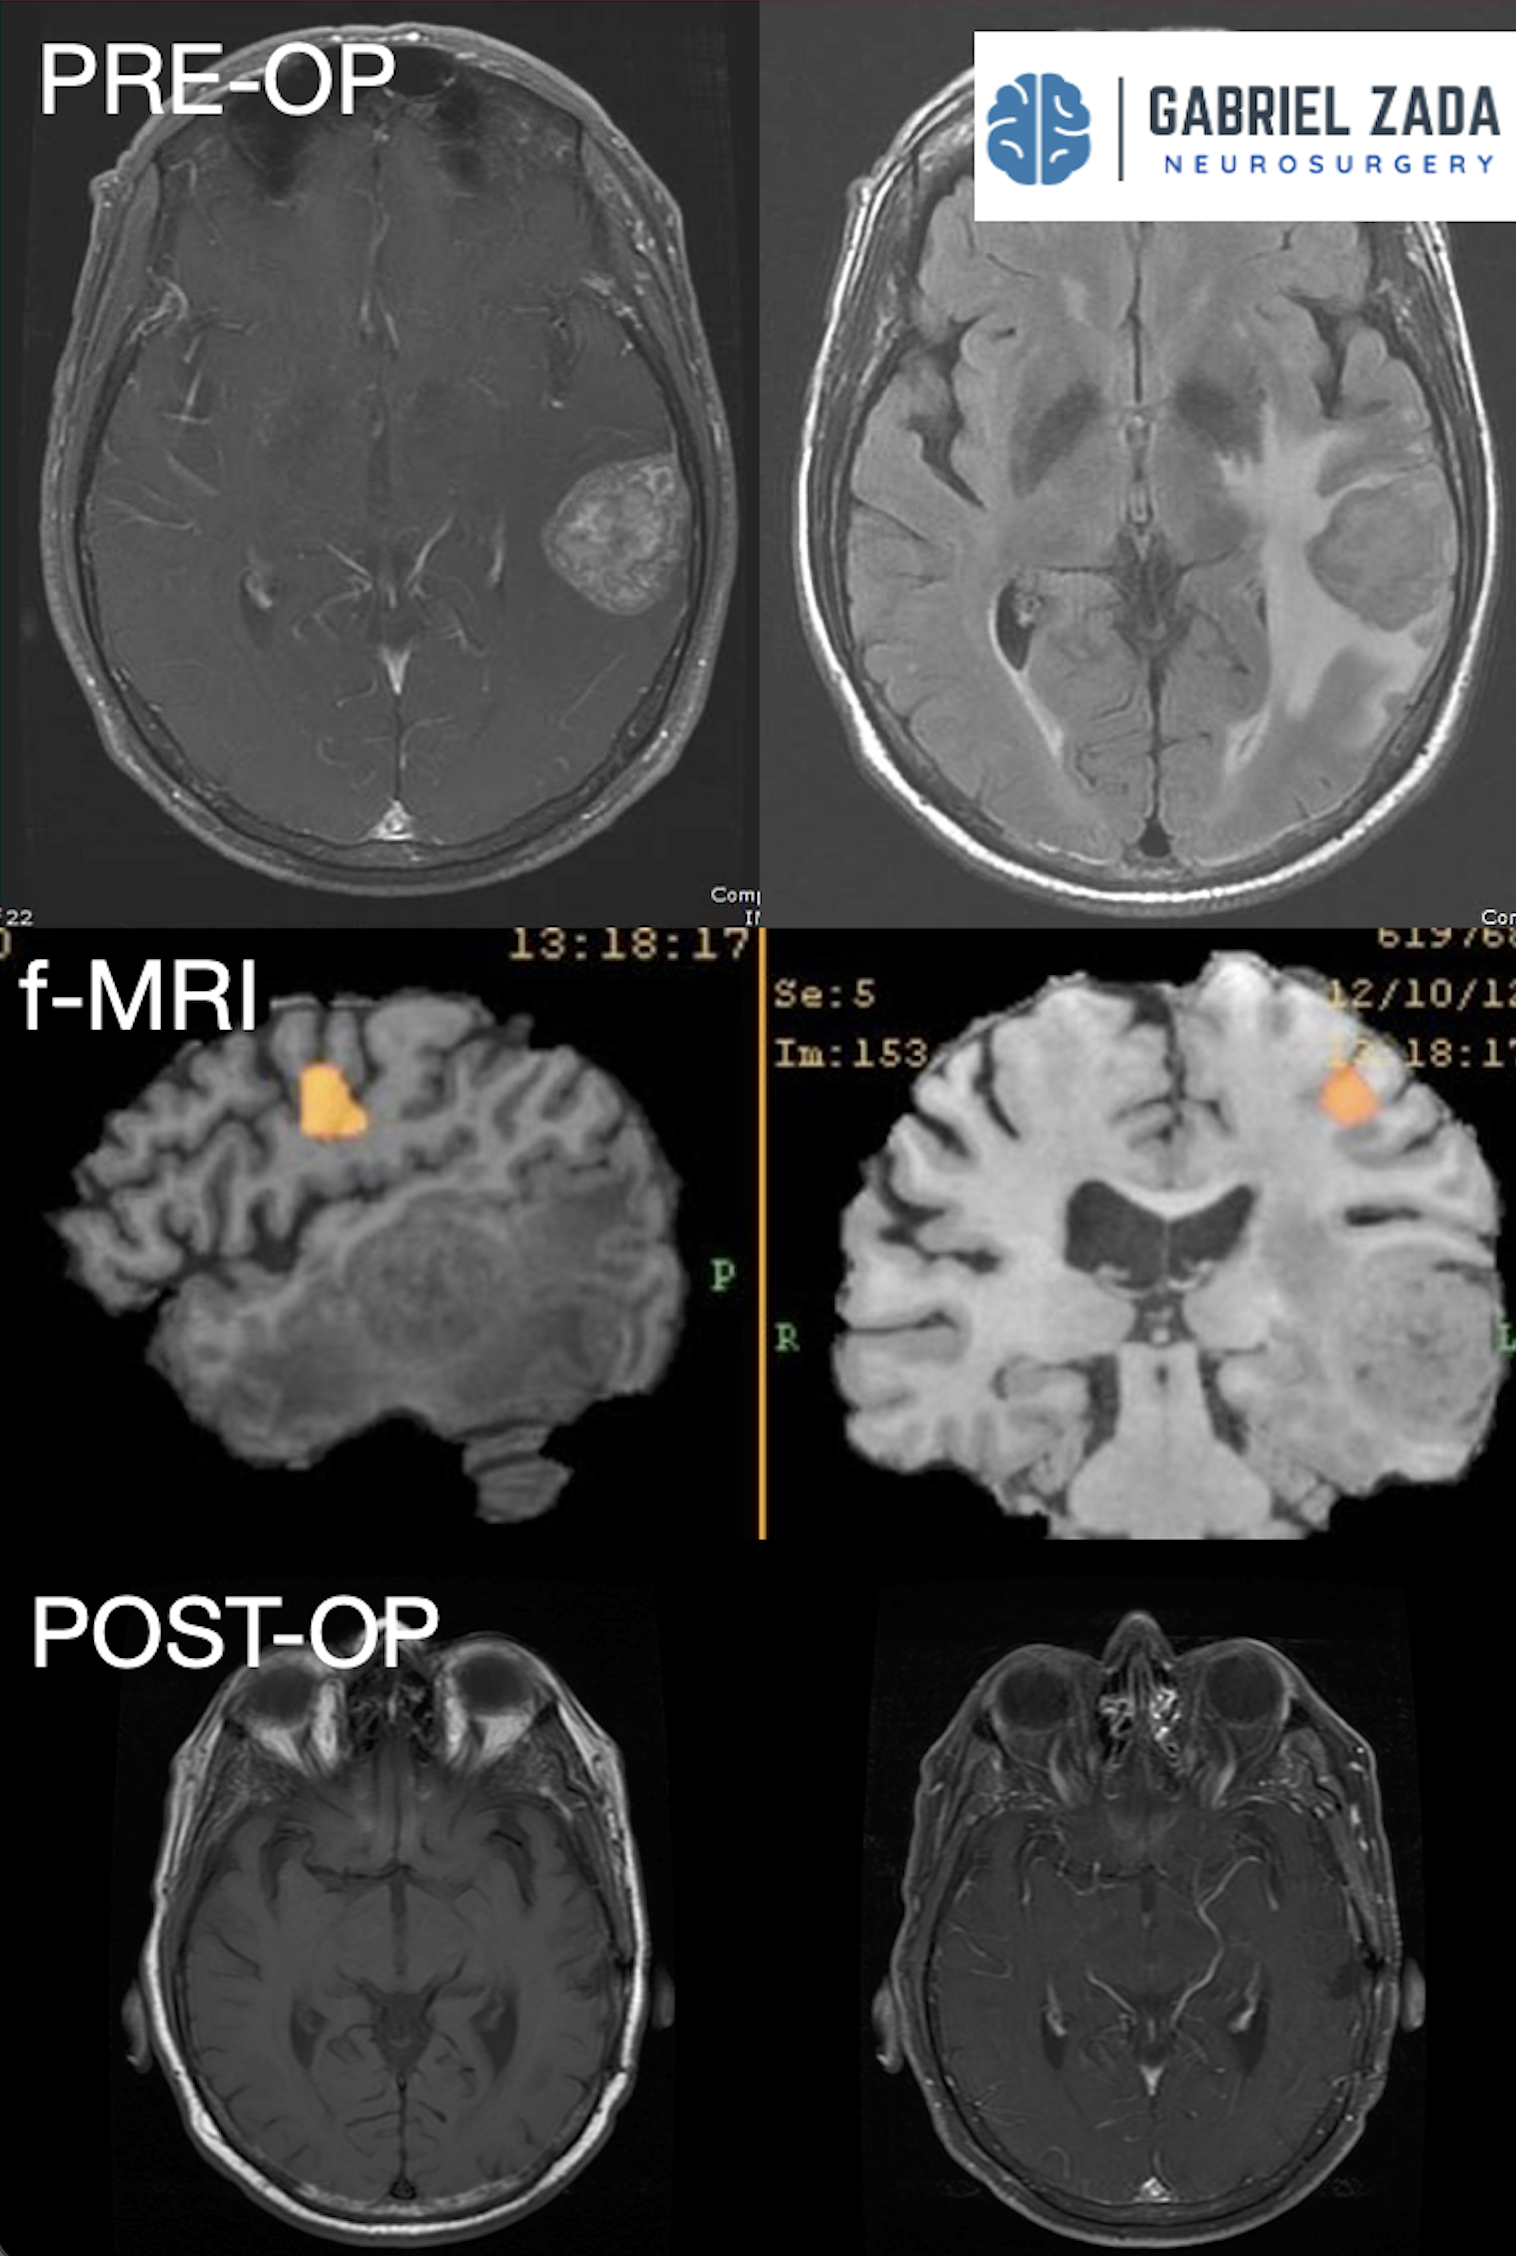

Explore this comprehensive gallery featuring pre‑ and post‑operative imaging of patients with skull‑base tumors treated by Gabriel Zada, MD, MS, FAANS, FACS. These cases highlight Dr. Zada’s expertise in advanced neurosurgical techniques and outcomes.

*Representative cases shown for educational purposes. All images de-identified. Individual results vary.